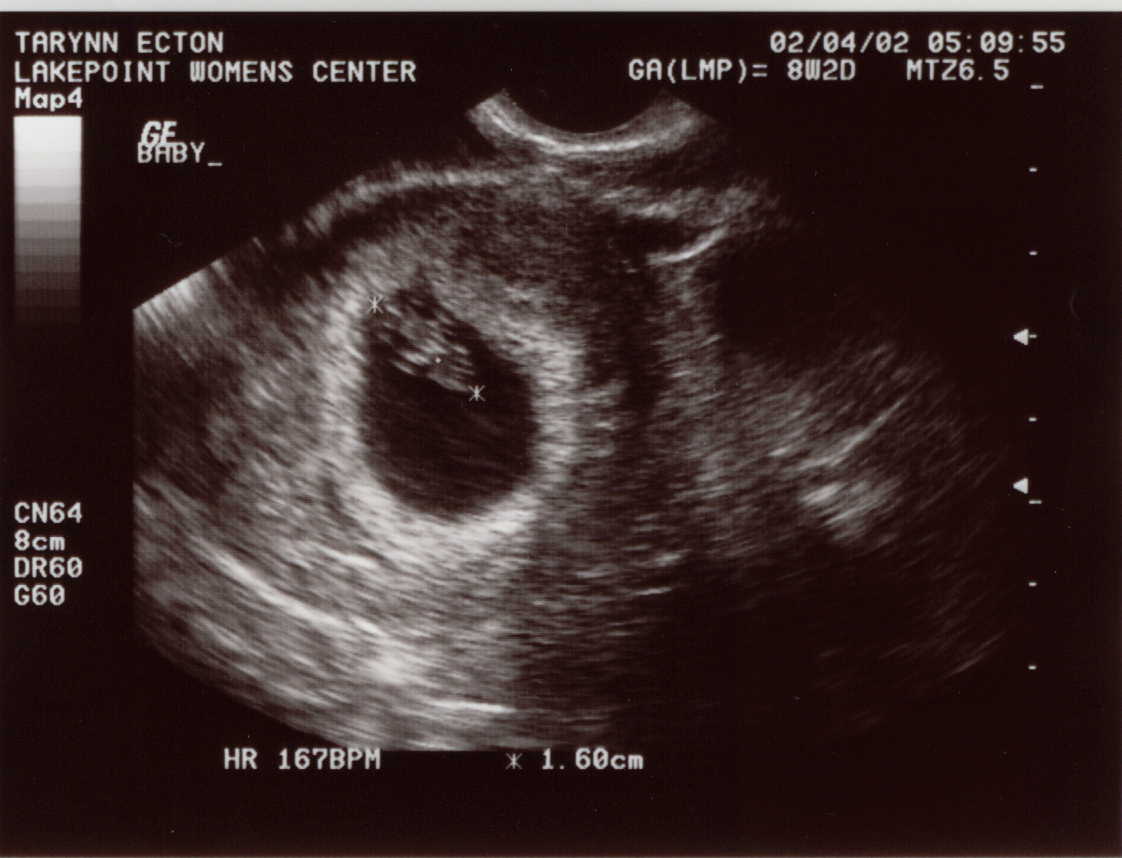

Baby Pictures!

First Sonogram, taken 02-04-02.